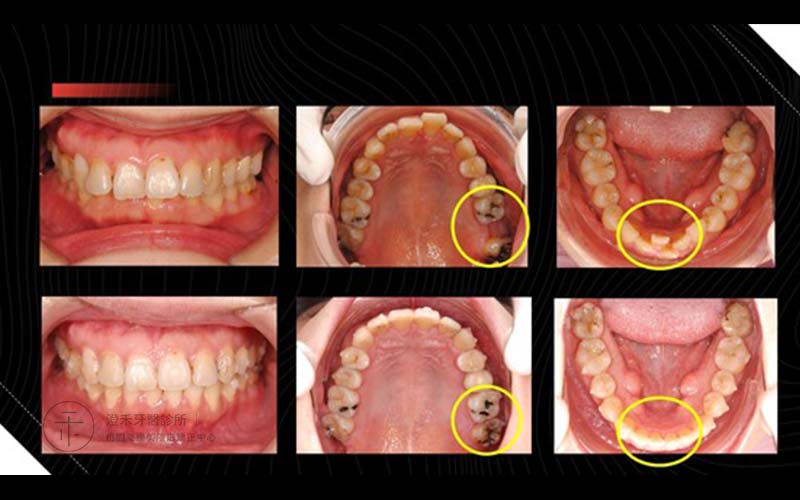

案例四

19歲,學生,牙弓窄沒有多餘空間使牙齒正常發育,造成齒列擁擠,使前牙牙齒有些旋轉及前後交疊。牙齒凌亂的情況下,會有許多死角不易清潔,長期下來容易造成蛀牙。不僅清潔不易,還會影響美觀。雙重情況下,透過矯正方式。翁同學經過數月與診所配合,牙齒排列整齊了,口腔照護也變得方便許多,重點是笑起來變得更甜更美!